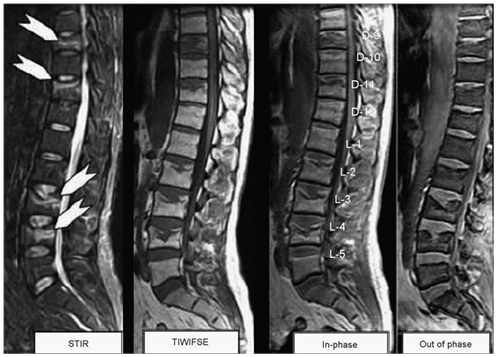

Establishing the accurate diagnosis is of great importance in determining treatment, surgical intervention, and prognosis. T1- and T2-weighted sequences without or with fat saturation show similar signal intensities for both benign osteoporotic and neoplastic fractures [Figure 1 & 2]. Thus, the morphology of bone marrow replacement has been evaluated for prediction of the benign or pathologic cause of a fracture. Paravertebral soft-tissue masses [Figure 2] and infiltration of posterior elements [Figure 2] are the most reliable MRI signs of a malignant fracture.10

Figure 1 Multiple vertebral benign osteoporotic wedging, STIR sequence shows marrow edema parallel to the end plate (white arrows) of D9, D11, L3 and L4 vertebrae with corresponding enhancement on T1-gadolinium fat sat images. All show significant signal drop on out of phase images consistent with benign collapse.

Ragab et al. 7 established the cut-off value of the signal intensity drop on chemical shift (MRI) to obtain appropriate sensitivity, specificity and cut off value to differentiate osteoporotic from neoplastic wedging of the spine. In their study a total of 40 patients were recruited, 20 with osteoporotic wedging [Figure1] and 20 neoplastic [Figure 2 & 3]. In their study the authors observed a substantial reduction in signal intensity in all lesions in both groups. The proportional changes observed in signal intensity of bone marrow lesions on in-phase compared with out-of-phase images showed significant differences in both groups (P < 0.05). At a cut-off value of 35%, the observed sensitivity of out-of-phase images was 95%, specificity was 100%, positive predictive value was 100% and negative predictive value was 95.2%. In contrast to the study by Ragab et al.7 Zajick et al.15 suggested that a decrease in signal intensity greater than 20% on out-of phase images compared with in-phase images should be used as a cut-off threshold for normality to allow distinction between benign and neoplastic vertebral marrow lesions.